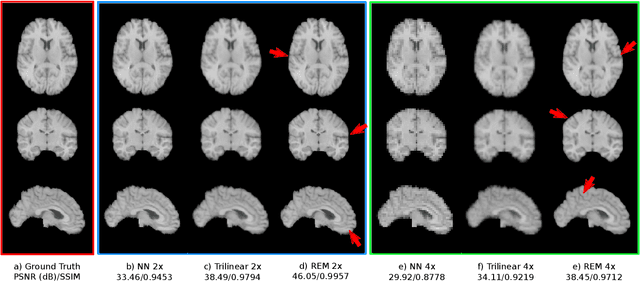

Abstract:Image registration is a fundamental task for medical imaging. Resampling of the intensity values is required during registration and better spatial resolution with finer and sharper structures can improve the resampling performance and hence the registration accuracy. Super-resolution (SR) is an algorithmic technique targeting at spatial resolution enhancement which can achieve an image resolution beyond the hardware limitation. In this work, we consider SR as a preprocessing technique and present a CNN-based resolution enhancement module (REM) which can be easily plugged into the registration network in a cascaded manner. Different residual schemes and network configurations of REM are investigated to obtain an effective architecture design of REM. In fact, REM is not confined to image registration, it can also be straightforwardly integrated into other vision tasks for enhanced resolution. The proposed REM is thoroughly evaluated for deformable registration on medical images quantitatively and qualitatively at different upscaling factors. Experiments on LPBA40 brain MRI dataset demonstrate that REM not only improves the registration accuracy, especially when the input images suffer from degraded spatial resolution, but also generates resolution enhanced images which can be exploited for successive diagnosis.